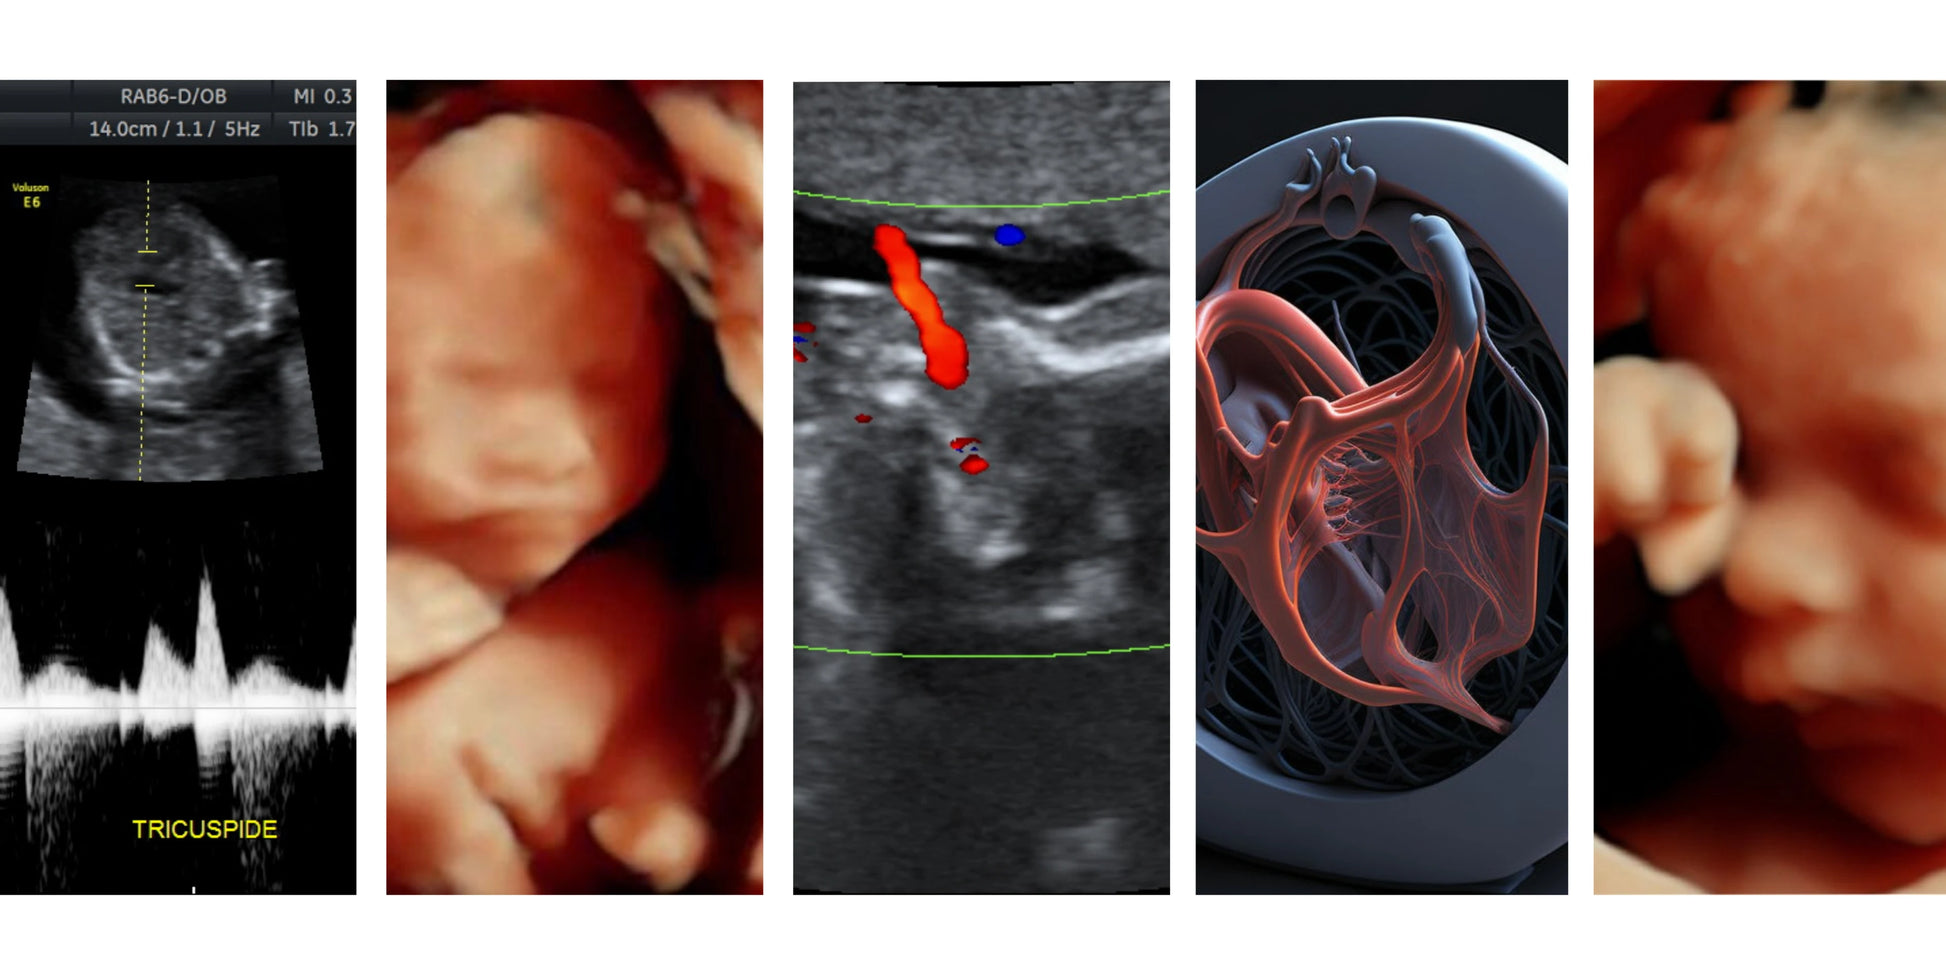

El ultrasonido estructural 4D es una técnica avanzada de imagenología que utiliza ondas de sonido para crear imágenes tridimensionales en tiempo real de su bebé dentro del útero. Este tipo de ultrasonido se realiza típicamente durante el segundo trimestre, entre las semanas 18 a 25 de gestación, y permite evaluar el desarrollo y la anatomía de su bebé, así como identificar cualquier anomalía estructural o problema de salud potencial.

Evaluación exhaustiva del desarrollo y la anatomía de su bebé para garantizar su bienestar y detectar cualquier problema de salud.